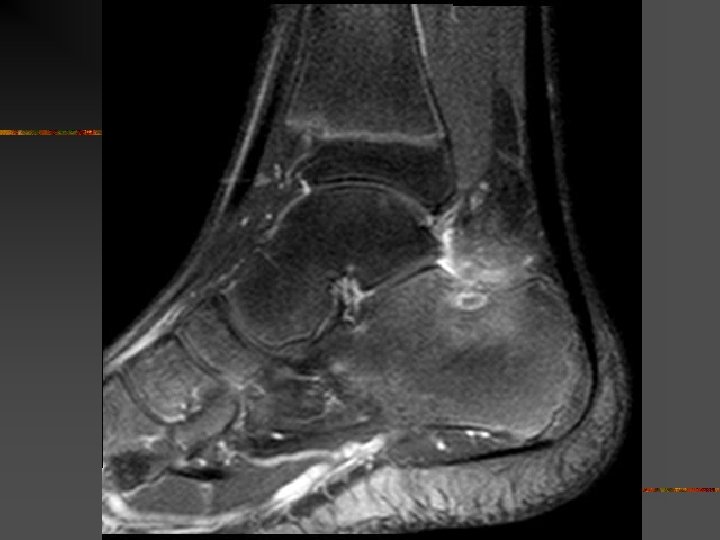

SCP microtraumatique : Lésions n n n Inflammation récessus capsulo-ligamentaires postérieurs Arthrose talo-crurale ou sous-talienne postérieure # de stress tibio-talienne postérieure Lésion ostéo-chondrale dôme talien postérieur Tendinopathie Fléchisseur Propre de l’Hallux (TS > fissures IT)

SCP : Diagnostic = Clinique Mais le diagnostic « lésionnel » = imagerie But : Préciser : - anatomie - définir lésion n Moyens : - RX - Echo (tendon FPH) - CT , arthro. CT, IRM , scinti n (surtout si trauma pour exclure # méconnue)

SCP : Diagnostics différentiels Avec flexion plantaire douloureuse - Tendinopathies du Long Fléchisseur de l’Hallux . Situation : gouttière du processus post. Du talus ( tunnel ostéo-fibreux non extensible) . Facteur favorisant : jonction MT basse - jonction N = niv. Art. tibio-talienne - jonction basse = niv. Talus ou face médiale calca. n (néanmoins anomalies le plus svt asymptomatiques) - Lésion ostéochondrale dôme talus ou du pilon tibial (séq. T , kyste , …)